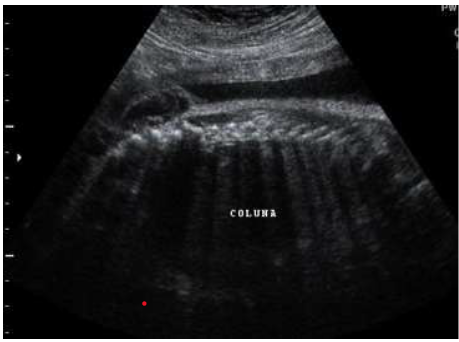

Paciente 24 anos, secundigesta, apresentando idade gestacional de 23 semanas, gestação não planejada, encaminhada para avaliação morfológica do segundo trimestre.

Após analisar as imagens abaixo, quais os sinais ecográficos encontrados e qual a hipótese diagnóstica?